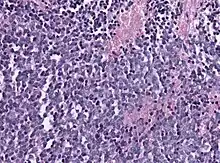

Histology of pineoblastoma

Biopsy is required for diagnosis. Pineoblastomas appear as high grade, highly cellular, small blue cells histologically. Features of aggressive malignancies can be seen, like high nucleus-to-cytoplasm ration, poorly differentiated cells, high mitotic activity, and necrosis.[13][3] Homer Wright, or neuroblastic, and Flexner-Wintersteiner, or retinoblastic, rosettes can also be seen. In contrast to other masses of the pineal gland, pineocytomatous rosettes are not present.[13] Immunohistochemistry staining will reveal neuronal, glial, and photoreceptor marker positivity. This includes synaptophysin, neurofilament protein, and CRX, a specific pineal or retinal marker, positive staining.[13][7]